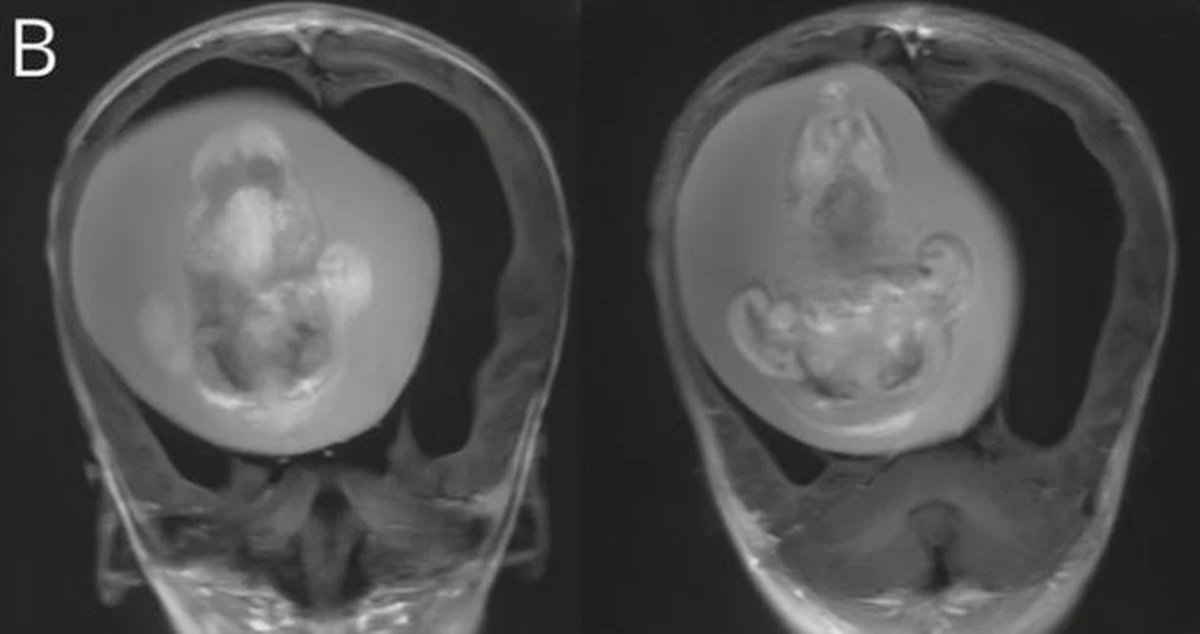

Po przeskanowaniu czaszki medycy znaleźli w głowie dziecka bliźniaka pasożytniczego.

Lekarze z Szanghaju usunęli płód z mózgu dziecka podczas skomplikowanej operacji.

Miał 10 centymetrów, miał zaczątki ramion, kręgosłupa, kości nóg.